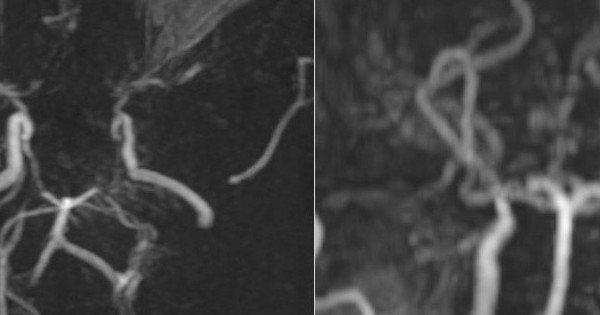

Stress kéo dài khiến cơ thể liên tục tiết hormone adrenaline và cortisol, làm tim đập nhanh, huyết áp tăng, gây viêm mạn tính – nền tảng dẫn đến xơ vữa động mạch, nhồi máu cơ tim hoặc đột quỵ.